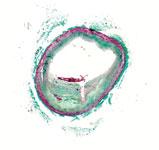

An example of OCT showing a stent with neointimal growth over the stent struts. The struts appear as bright spots.

While IVUS provided better information than angiography alone, poor image quality led manufacturers to begin researching other imaging technologies. OCT was brought to market first in Japan by LightLab Imaging in 2008, and launched in the United States in May 2010. OCT uses near infrared light to project images of the vessel wall and lumen. Due to the high frequency associated with the light signal, image resolution is 10 times greater than that of IVUS, leading to better views of stent apposition and thrombus detection. Reduction in stent mal-apposition, which is associated with late stent thrombosis (LST) and better resolution for neo-intimal tissue growth and in-stent restenosis are some of the key advantages of OCT.